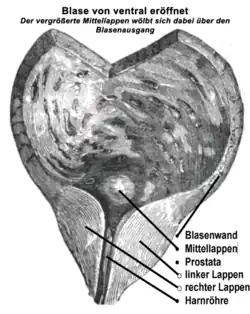

Die Harnröhre verläuft unterhalb der Blase ein Stück weit durch die Vorsteherdrüse. Diese besteht aus einem linken und rechten Lappen sowie einem hinter der Harnröhre gelegenen Anteil, der als Isthmus prostatae oder als Mittellappen bezeichnet wird. Eine BPH entsteht durch eine Zellvermehrung in der sogenannten Übergangszone und den um die Harnröhre herum angelegten (periurethralen) Drüsen. Dabei vermehren sich jedoch nicht ausschließlich die Drüsenzellen, sondern auch Bindegewebe und Muskelzellen – deshalb ist auch der früher geläufige Begriff Prostataadenom fachlich nicht korrekt. Bei entsprechend ausgeprägter Vergrößerung wird dabei die periphere Zone der Prostata – sie macht normalerweise drei Viertel der Organmasse aus – nach außen abgedrängt und dabei so weit gedehnt, dass sie im Schnittbild das Organ nur noch als dünne Schicht, die sogenannte chirurgische Kapsel, umgibt. Der Isthmus prostatae (Lobus medius, Mittellappen) kann sich zudem weit in das Blaseninnere vorwölben.

Das Gewicht der Prostata beträgt normalerweise etwa 20 bis 25 Gramm. Bei Vorliegen einer BPH wiegt die Prostata 30 bis 150 Gramm. In der Summe stellt die BPH ein Hindernis für den Harnabfluss aus der Blase dar (subvesikale Obstruktion, also unterhalb der Harnblase). Bei normalem Miktionsdruck (Druck, den die Blasenwand aufbaut, um den Harn auszutreiben) ist dann die Harnflussrate reduziert. Ein kompensatorisch erhöhter Miktionsdruck kann zu einer Balkenblase oder autonomen Detrusorkontraktionen (Overactive Bladder, OAB) führen.[10][11] Zusätzliche Bedeutung kommt dem sich in das Innere der Harnblase vorwölbenden (daher im klinischen Sprachgebrauch auch als intravesikal gelegen bezeichnet[12]) vergrößerten Mittellappen zu, der den Blasenausgang verlegen kann. Dieser Effekt kann unabhängig von der unterhalb der Blase bestehenden Einengung der Harnröhre auftreten.